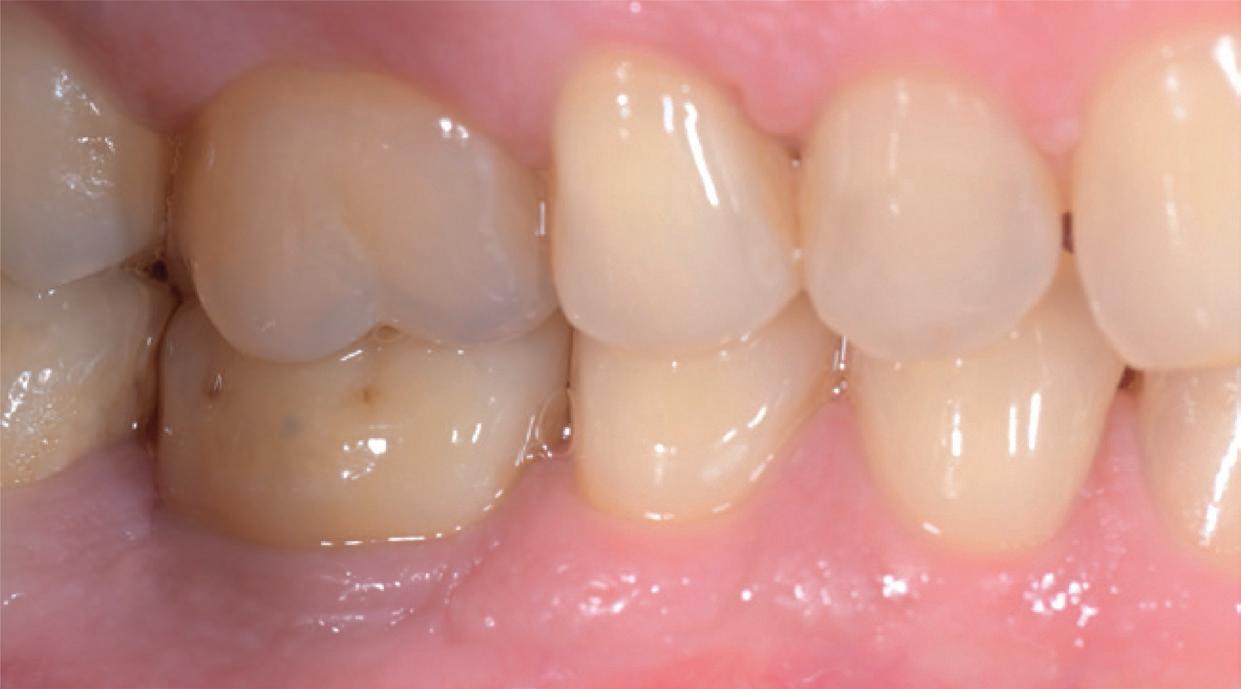

The standardisation of treatment procedures has resulted in less emphasis on craftmanship. I have quite a few gold restorations in my own mouth, two of which were placed there by a very fine dentist in 1968, both are still intact with no breakdown around the margins and both the teeth are functioning well, despite one of them having been root treated with silver points at the time. I take regular radiographs and there are absolutely no problems. I placed a number of gold restorations in my wife’s mouth before we were married in 1973 and they, too, are all still functioning well. And yet my laboratory, which

employs more than 30 technicians, has only one person who is still capable of producing good metal margins and despite all the emphasis on digital restorations and aesthetics, the dentists that I treat as patients prefer gold in their own mouths and for their families wherever possible.